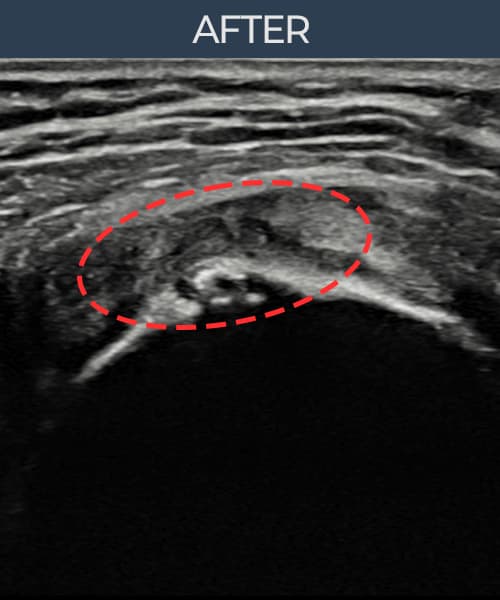

[経過期間: 23.07.18~23.09.14]

[縫縮術] 超音波検査にて左 棘上筋腱 광범위 部分断裂(15mm × 6mm (腱厚の約70%欠損))を確認。縫縮術施行後、腱の連続性が回復し、日常生活に復帰されました。